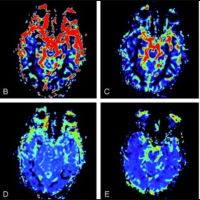

Hipertensão Idiopática Intracraniana

Ao optarmos pelo tratamento endovascular da hipertensão idiopática intracraniana/ pseudotumor....